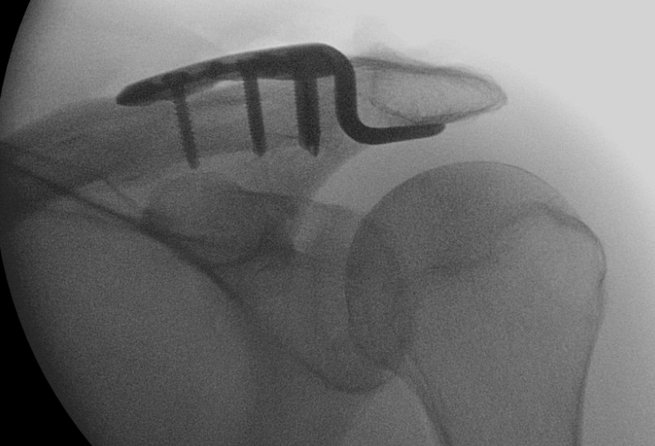

Eine AC-Gelenksprengung ist eine Verletzung des Schultereckgelenks (Akromioklavikulargelenks), meist nach einem Sturz direkt auf die Schulterspitze. Dabei zerreißen – je nach Schweregrad – die Bandverbindungen zwischen Schlüsselbein und Schulterblatt (AC- und/oder CC-Bänder). Typisch sind eine sichtbare Stufe über dem Schultereckgelenk („Klaviertastenphänomen“) und Bewegungsschmerzen bei Armhebung.

Leichte Formen (Rockwood I–II) werden konservativ behandelt, meist mit Ruhigstellung und frühzeitiger Mobilisierung.

Höhere Grade (III–V, selten VI) erfordern häufig eine operative Stabilisierung, insbesondere bei jungen, aktiven oder sportlich ambitionierten Patientinnen und Patienten.

Operative Verfahren

Ziel der Operation ist die anatomische Wiederherstellung der Position des Schlüsselbeins und die Stabilisierung des korakoklavikulären Bandapparates.

Gängige Verfahren sind:

• Faden-Button-Systeme (z. B. TightRope, Dog Bone, Twin Tail):

Minimalinvasiv arthroskopisch oder offen durchgeführt. Zwei kleine Bohrkanäle verbinden das Schlüsselbein mit dem Rabenschnabelfortsatz (Coracoid).

Vorteile: keine Metallentfernung nötig, geringere Weichteilirritation, schnellere Rehabilitation.

• Hakenplatte:

Offene Stabilisierung, bei der eine Metallplatte unter das Akromion greift und das Schlüsselbein fixiert. Gute Stabilität, jedoch häufig Irritationen subakromial, weshalb eine Metallentfernung nach ca. 3 Monaten empfohlen wird.

Aktuelle Metaanalysen zeigen, dass Faden-Button-Systeme eine vergleichbare Stabilität bei geringerer Reoperationsrate und weniger subakromialen Beschwerden bieten als die Hakenplatte.